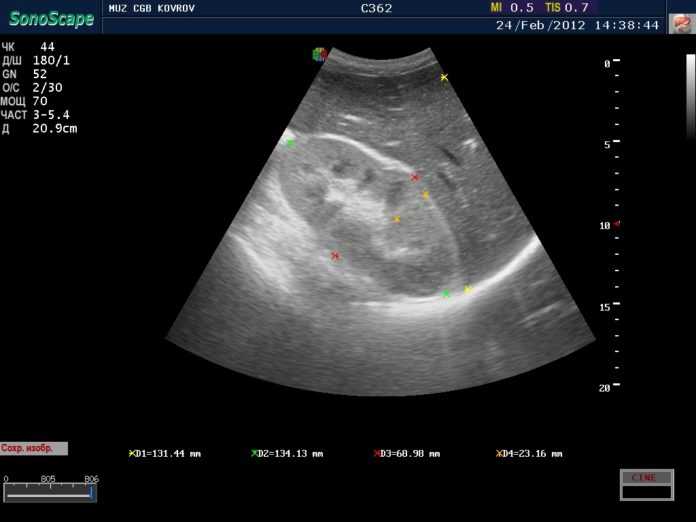

Основным способом диагностики диффузных изменений считают УЗИ. В описании результатов обычно пишут, что это такое, указывая эхографические признаки патологии.

Среди них:

- утолщение тканей;

- истончение лоханки;

- невозможность увидеть вену;

- слабая эхогенность;

- нечеткий контур почечной паренхимы;

- нарушение кровоснабжения;

- наличие жидкости;

- изменение размера почек;

- кисты;

- опухоли;

- появление в сосудах тромбов;

- обратный кровоток в артерии.